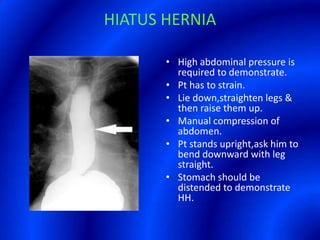

This document provides information about a barium swallow procedure. It begins with an introduction and overview of the embryology and anatomy of the pharynx and esophagus. It then describes the procedure itself, including preparation, technique, views obtained, and indications. Specific conditions that may be examined include pharyngeal and esophageal webs, foreign body impaction, scleroderma, dysphagia, mediastinal masses, and carcinoma. Diagrams are provided to illustrate normal anatomy and various pathological findings.